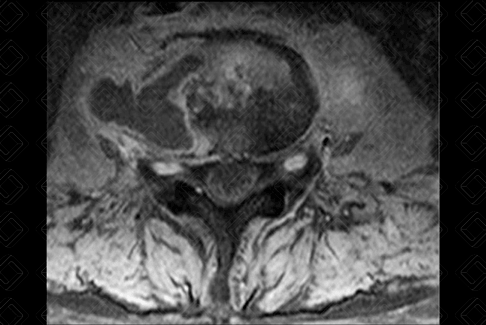

Texto alternativo para a imagem Créditos: Dra. Elazir Mota - Rio de Janeiro/RJ

Descrição da figura: Coleção paravertebral de paredes finas e limites bem definidos na sequência T1 pós-contraste. Notar o exuberante realce periférico. Cultura do material puncionado revelou Mycobacterium tuberculosis .

• Ressonância magnética (RM) da coluna: Os achados de imagem em RM suspeitos para espondilodiscite tuberculosa são: acometimento subligamentar multissegmentar, massa/abscesso paravertebral de limites bem definidos, disco relativamente poupado em fases precoces, e realce/alteração de sinal heterogênea dos corpos vertebrais.